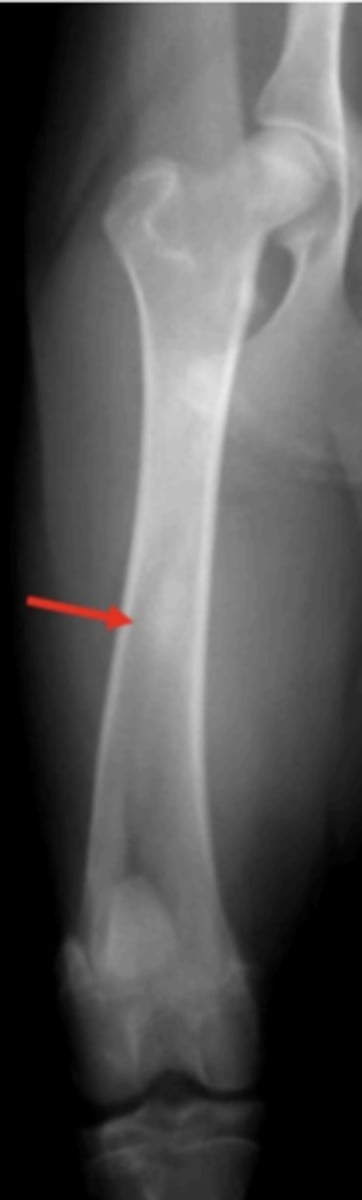

Hypertrophic osteodystrophy

6 month old Lab with distal limb swelling and the metaphysis is warm to the touch.- What is wrong with it?